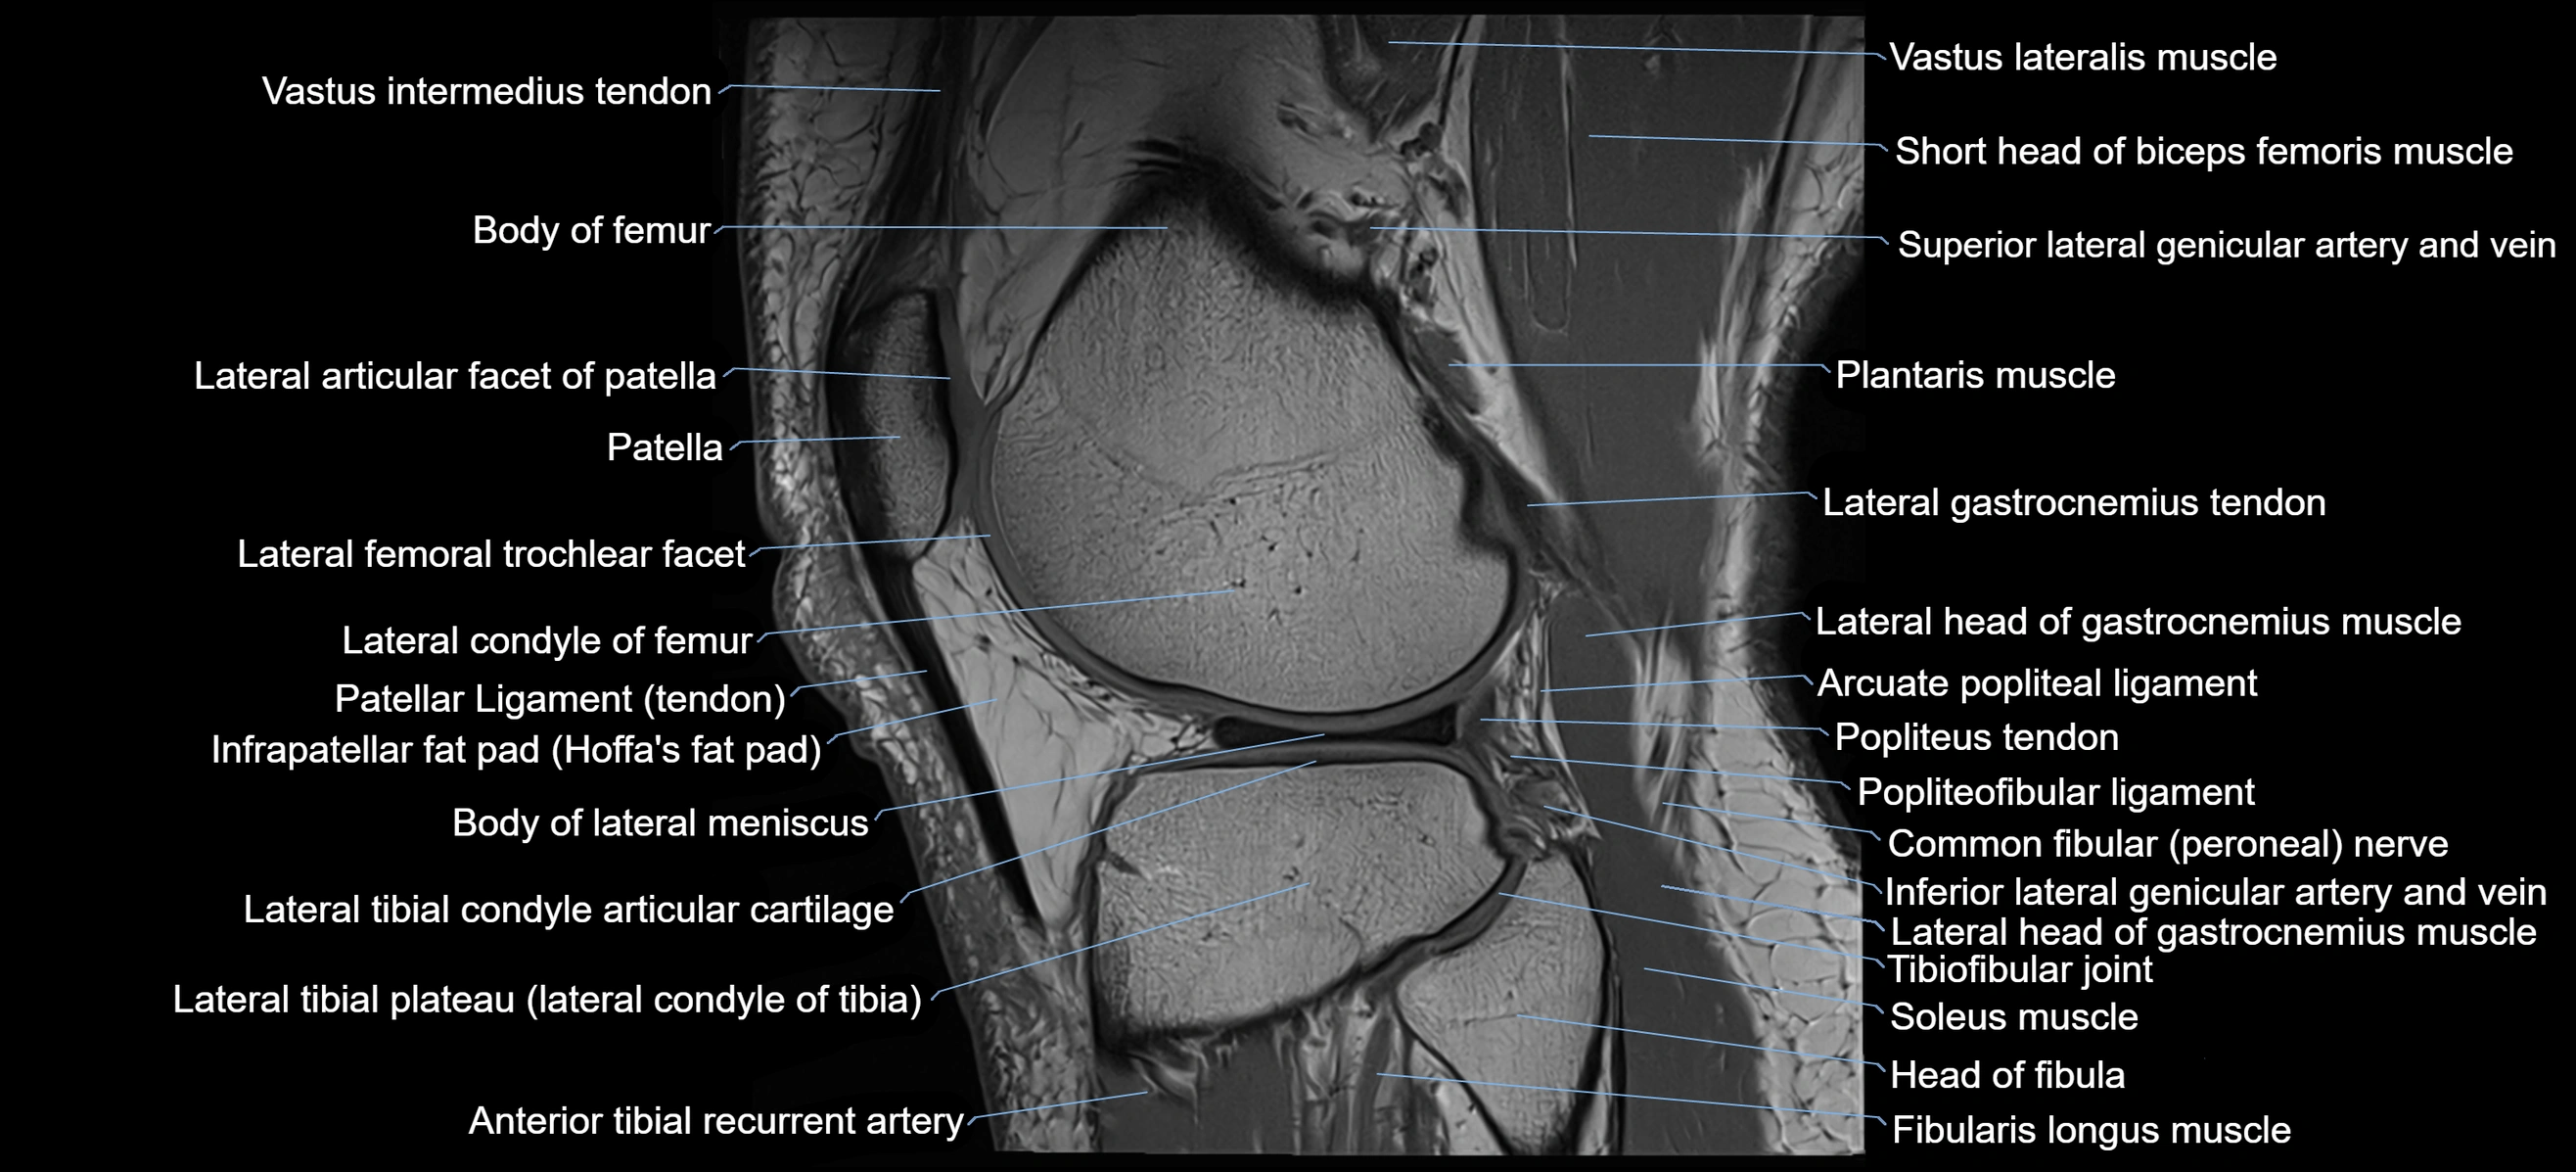

- Body of lateral meniscus

- Lateral articular facet of patella

- Lateral condyle of femur

- Lateral gastrocnemius tendon

- Lateral head of gastrocnemius muscle

- Lateral meniscus

- Lateral tibial plateau

- Patellar tendon (patellar ligament)

- Plantaris muscle

- Popliteus tendon

- Soleus muscle